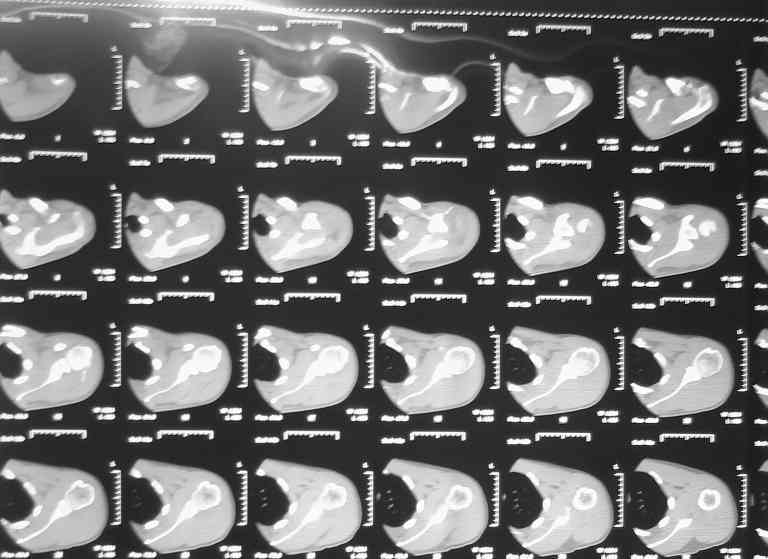

Множественные травмы скелета.(застарелый разрыв левого АКС)

Падение на очередной гонке. По рассказу пациента произошел вывих плеча, который доблестные мед. работники города Саранска вправили "наживую" прямо на стадионе. Больного не фиксировали. По приезду зафиксировали плечо в наружной ротации (см. фото). Сделали Кт (На серии КТ с толщиной срезов 3 мм в левой плечевой кости определяется отрыв большого бугорка, определяется линейный перелом клювовидного отростка левой лопатки без смещения отломков (стрелки). В полости сустава- небольшое количество жидкости. В головке плечевой кости определяется эностоз. Определяется краевые костные разрастания акромиального конца ключицы. Заключение: перелом левой лопатки и плечевой кости.) Возникли вопросы по дальнейшей фиксации: Стоит ли давать отведение? Ну и дальнейшая тактика ведения больного. Спасибо за внимание.